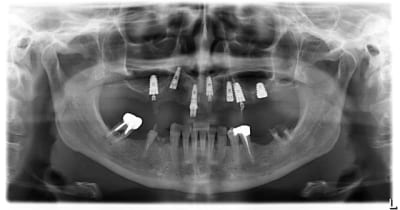

J'avais déjà posté ce cas me semble-t-il, mais je recommence car il est "pédagogique".

La patient consulte pour sa réhabilitation. Je me vois obligé de lui proposer un plan de traitement à base de "on dépave tout" (je conserve de 35 à 43). Puis sinus lift....Bref le traitement classique. Il y en avait pour 25k€ à la louche. C'est très cher j'en conviens.

Là je découvre un bridge provisoire en résine implanto-porté. Devant la mobilité de l'ensemble je prends une pano.

A la vue de cette dernière je lui demande ou elle a fait ça, tout en restant parfaitement confraternel.

D'un ton assez sec elle me répond que c'est "un ponte marocain qui fait ses études au states" (sans doutes plein de diplômes post graduate of michigan university au mur).

Je l'ai donc renvoyé vers son ponte de Rabat. Je n'ai plus jamais eu de nouvelle.

Implantmaroc zobbvd - Eugenol

Il y a mis de la bonne volonté, il a choisi différents implants pour s'adapter à chaque site...

Ou alors il a vidé ses fonds de tiroirs.

Y'en a quand même 2 qui ont évité un sinus ou une fosse nasale...C'est à ça qu'on voit que c'est un ponte.